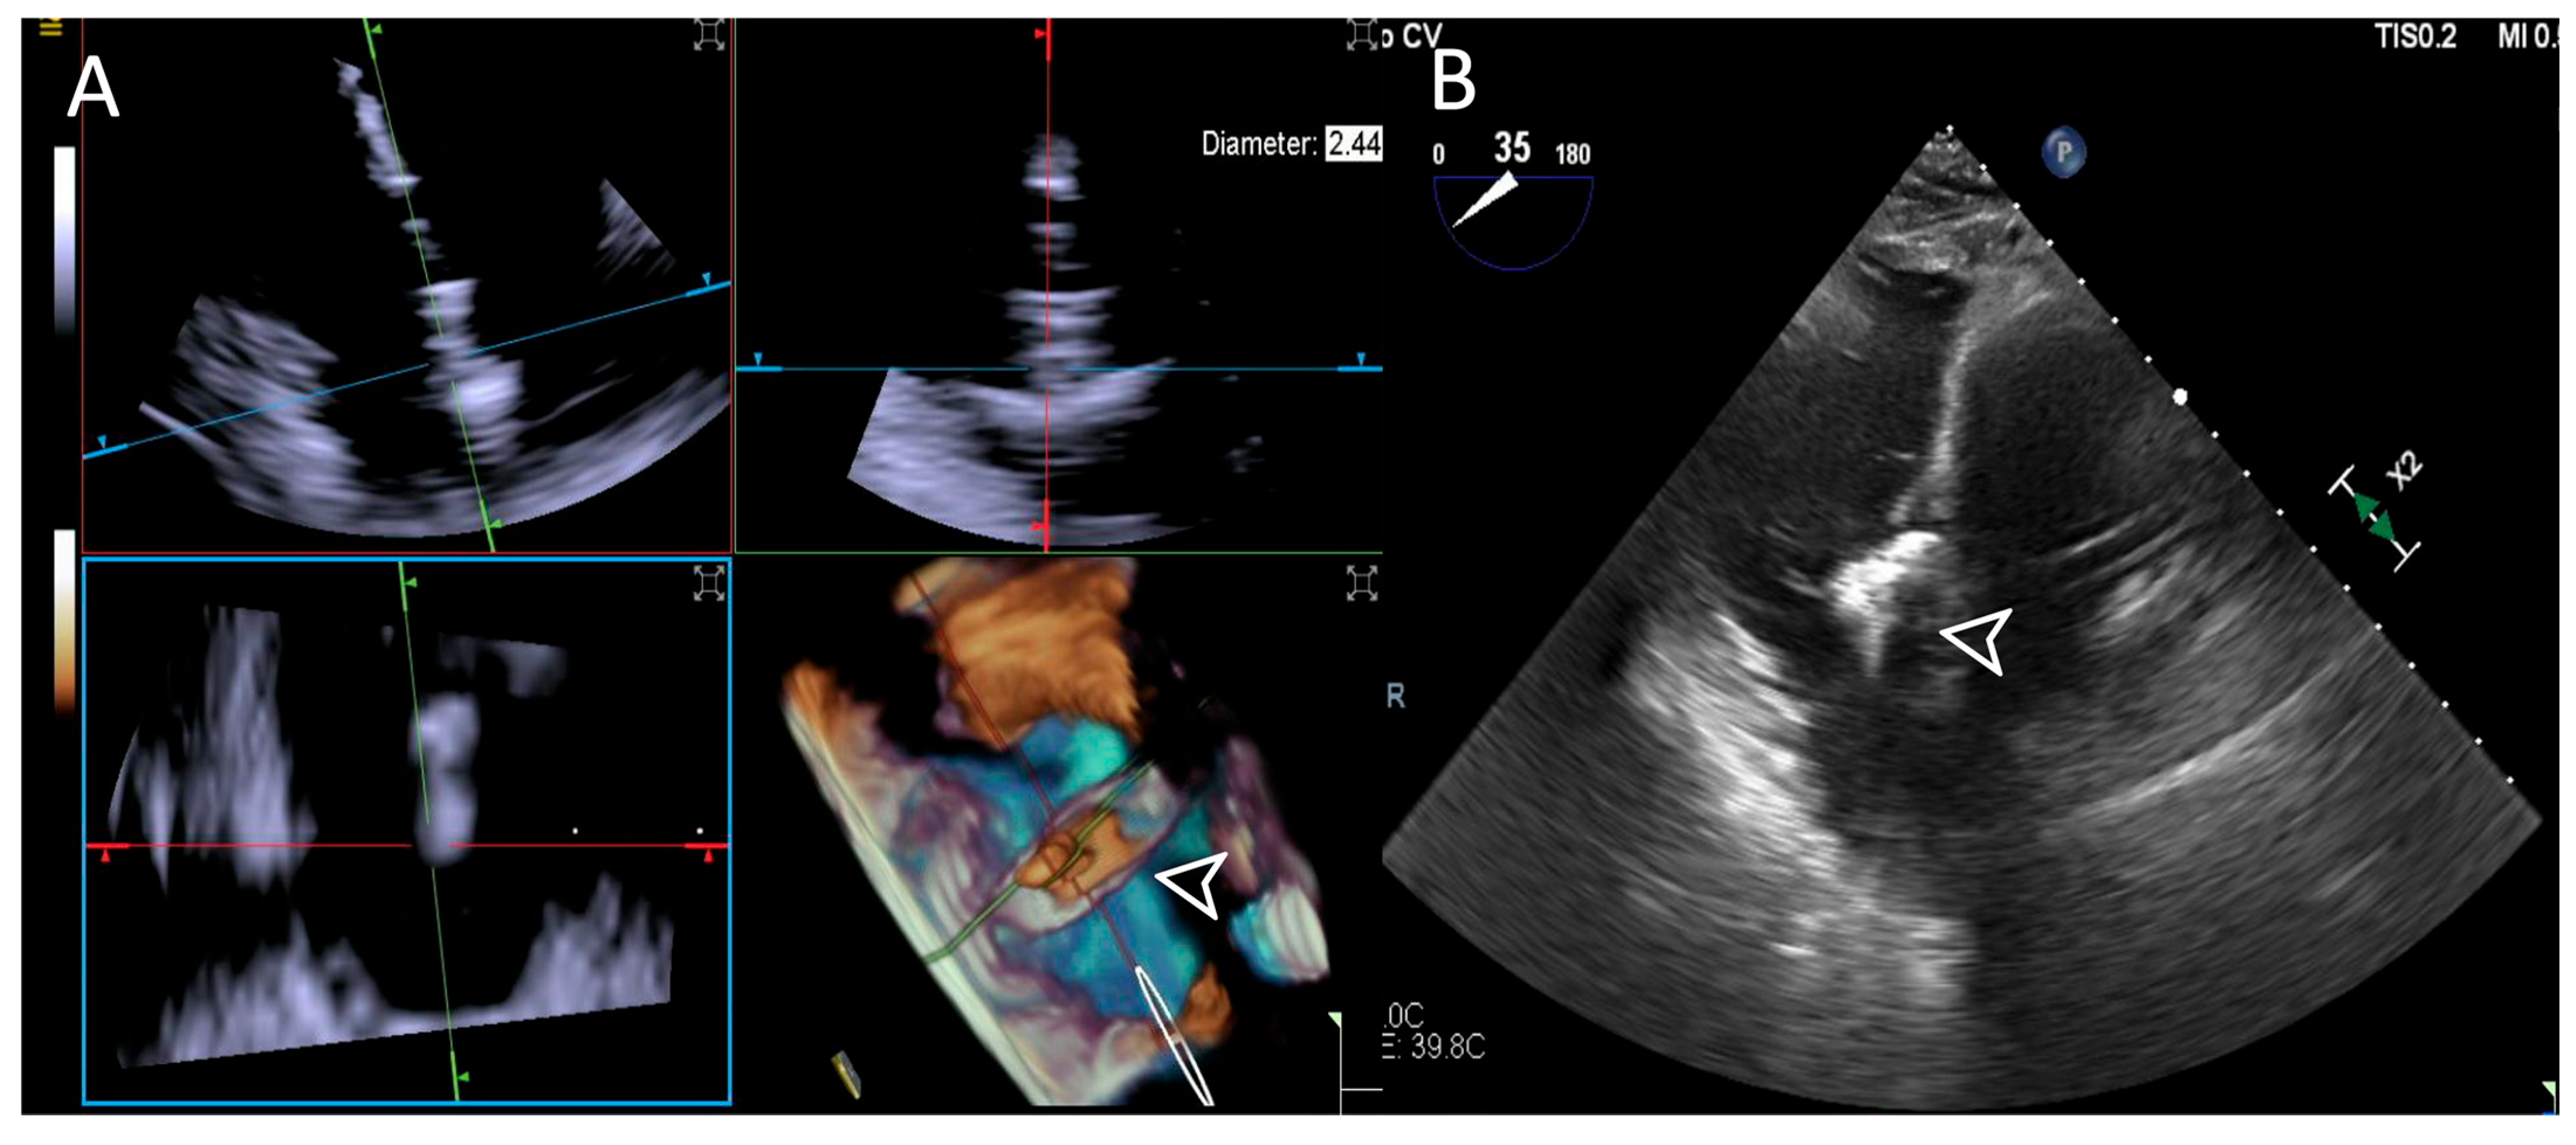

- Step number 4: ensuring perpendicularity and correct trajectory.

- Step number 3: steering and valve approach.